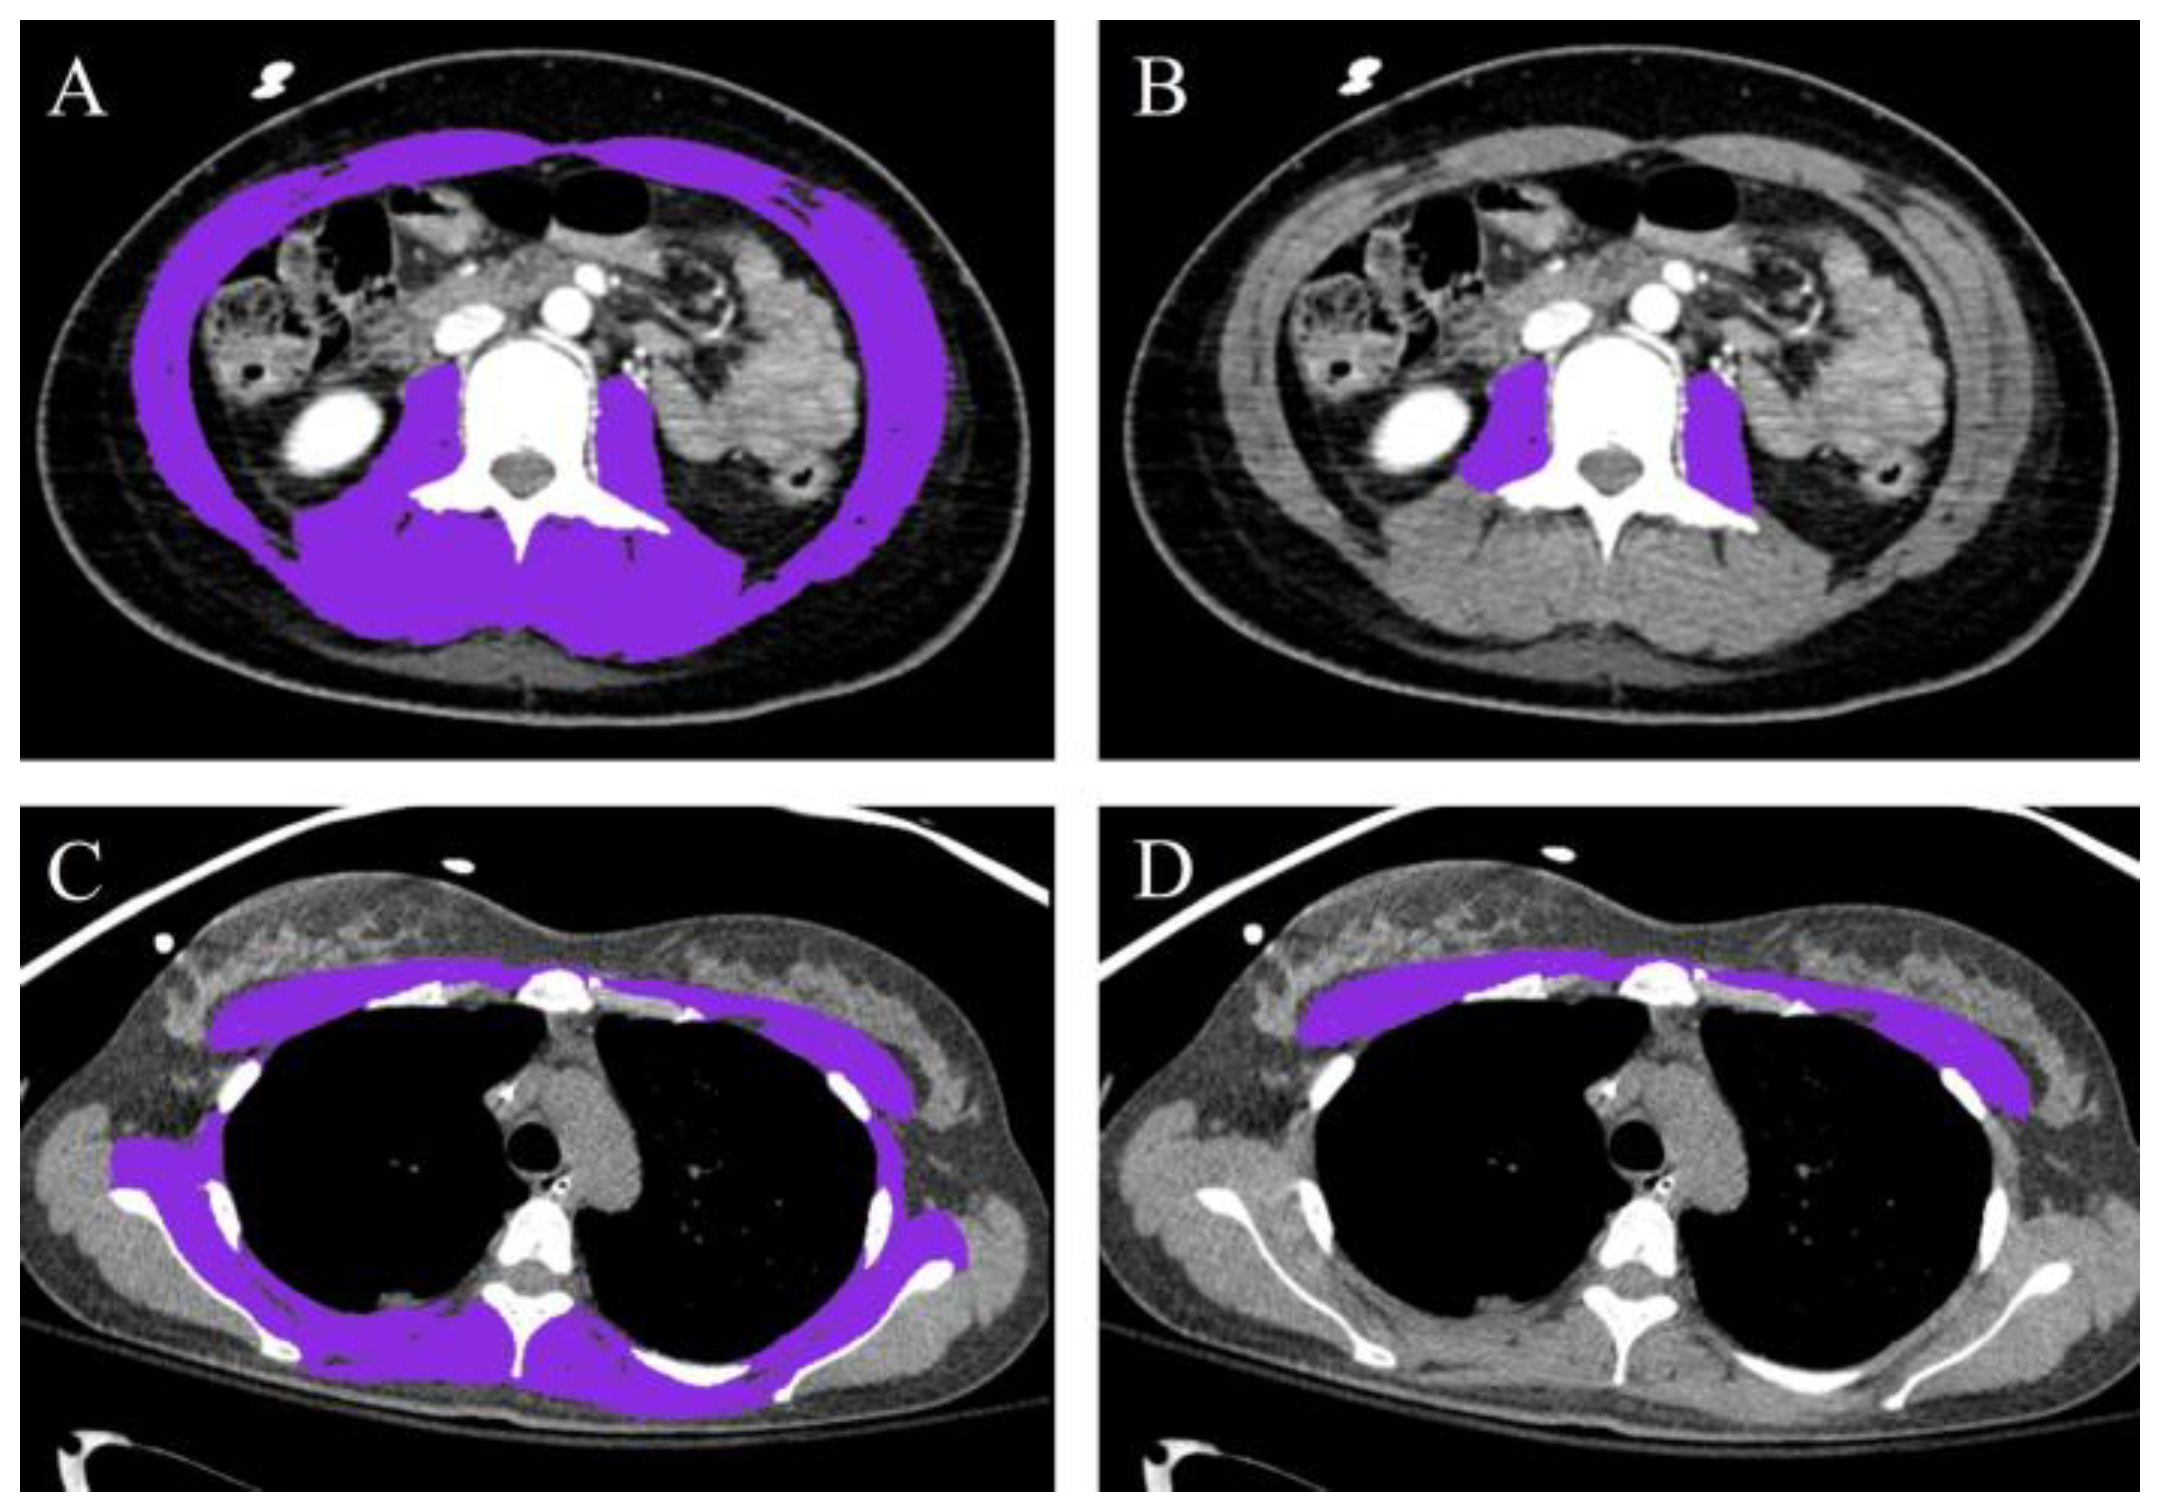

2.4. Muscle Mass Measurement